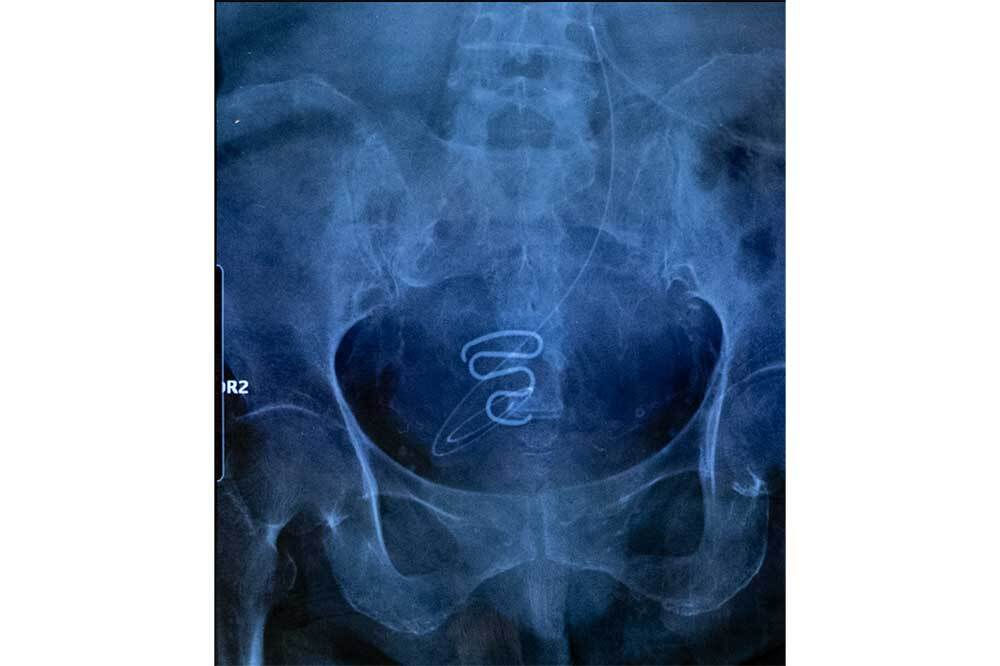

1966 ve 1975 yılları arasında Grönlandlı İnuit kadınlar, Spiralkampagnen (spiral kampanyası) olarak bilinen istemsiz bir doğum kontrol programının kurbanı oldular. Danimarkalı yetkililerin öncülüğünde, bazıları 12 yaşından küçük olan İnuit kız çocuklarına ve kadınlarına yaklaşık 4.500 rahim içi araç (spiral) yerleştirildi ve çoğu bu işlemin kendi rızaları olmadan yapıldığını söyledi. Bu kampanya ilk olarak 2022 baharında Danimarkalı bir podcast tarafından ortaya çıkarıldı ve belgeler yetkililerin Inuit nüfus artışını azaltmak için bu politikayı uyguladığını kanıtladı. Bu konuyla ilgili resmi bir soruşturma açıldı. Soruşturmanın 2024 yılı sonunda sonuçlanması bekleniyor.

© Juliette Pavy, France, Photographer of the Year, Professional competition, Documentary Projects, Sony World Photography Awards 2024